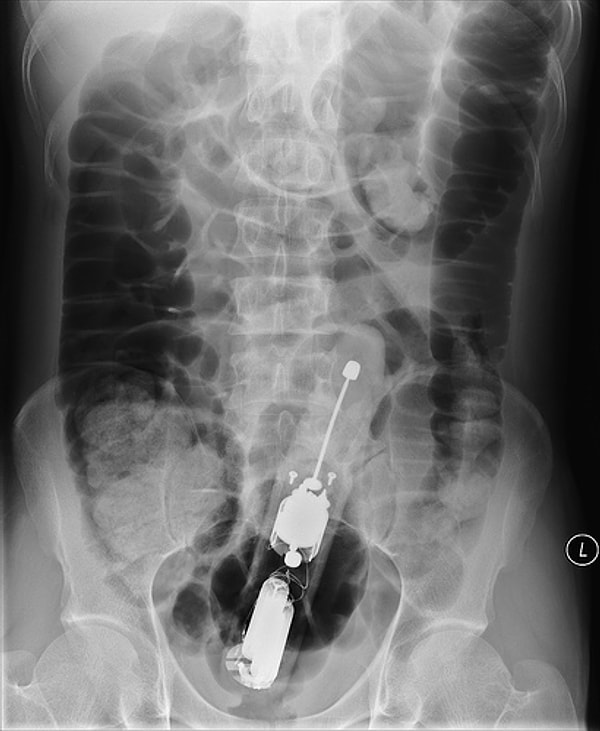

Удивительное рядом: 14 самых неожиданных вещей, найденных у пациентов при рентгене

В общем, ситуации самые разные. А уж предметы и подавно: зажигалки, фонарики, бутылки, гвозди. И даже живые лягушки 🙊